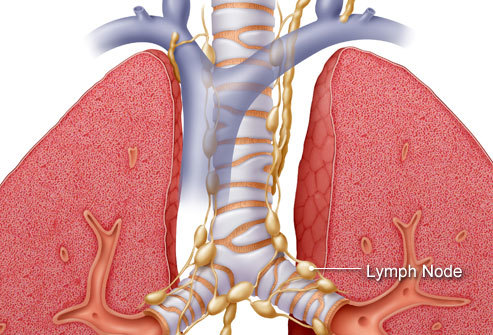

Các giai đoạn ung thư phổi

Mỗi loại ung thư phổi có cách xâm lấn khác nhau trong cơ thể. Như ung thư phổi tế bào nhỏ được chia thành hai giai đoạn: Giai đoạn giới hạn có nghĩa là ung thư được giới hạn trong một phổi và các hạch bạch huyết có thể ở gần vị trí khối u. Giai đoạn ung thư lan rộng có nghĩa là ung thư đã lan rộng khắp phổi hoặc ra các bộ phận khác. Ung thư phổi không phải tế bào nhỏ được chia thành từ 1 đến 4 giai đoạn, tùy thuộc vào việc khối u lan rộng đến đâu.